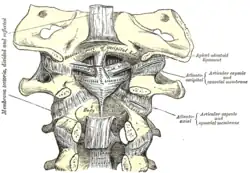

Occipital bone. Outer surface. Membrana tectoria, transverse, and alar ligaments.

Membrana tectoria, transverse, and alar ligaments. The anterior vertebral muscles.